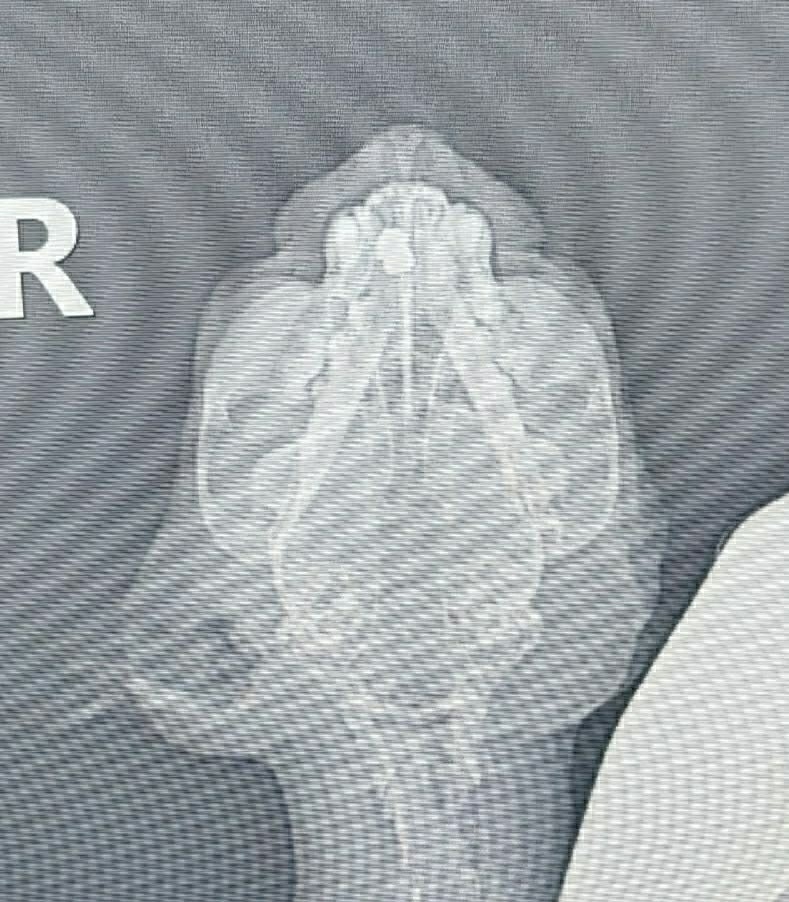

Она сама пришла к нам за помощью, по результатам анализов, карцинома😱Удалили слуховой проход, ушко оставили и зашили, стерилизовали, вылечили от лишая, по рентгену пуля в носу, но и это ещё не всё, диабет, сахар 19, 21😱 Сейчас Мусенька на передержке с медуходом на 1 месяц, для подбора дозировки инсулина и стабилизации сахара 💔Поэтому просим всех неравнодушных о помощи 🙏❤